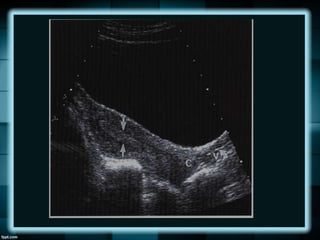

HIDROMETROCOLPOS Y

HEMATOMETROCOLPOS

La obstrucción del tracto genital origina la

acumulación de secreciones, sangre o ambas en

el útero y/o vagina.

La obstrucción puede ser congénita y con mayor

frecuencia se debe a un himen imperforado.

Otras causas incluyen septo vaginal, atresia

vaginal o cuerno uterino rudimentario.

HIDROMETROCOLPOS Y HEMATOMETROCOLPOS La obstruccióndel tracto genital origina la acumulación de secreciones, sangre o ambas en el útero y/o vagina. La obstrucción puede ser congénita y con mayor frecuencia se debe a un himen imperforado. Otras causas incluyen septo vaginal, atresia vaginal o cuerno uterino rudimentario.